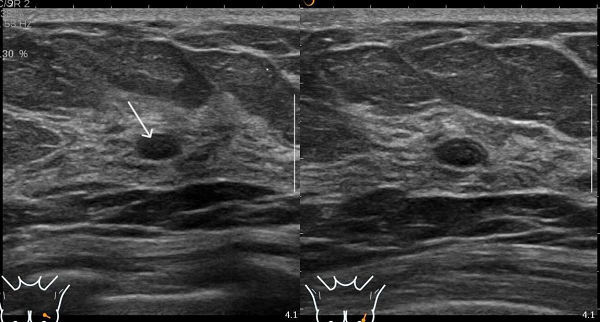

图2 患者A的超声表现图:(粗箭头处)乳腺囊肿,表现为无回声区;(细箭头处)乳腺实性结节,表现为低回声

图4 患者B的超声图像,显示未见钼靶所示钙化灶,但扫查到乳腺实性低回声结节(图中箭头处)